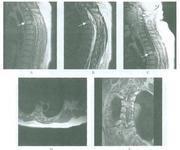

胸椎后纵韧带骨化症

628健康网为您分享有关胸椎后纵韧带骨化症的症状,胸椎后纵韧带骨化症的治疗方法,胸椎后纵韧带骨化症的预防知识,胸椎后纵...